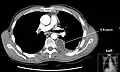

Masivo derrame pleural izquierdo (zona blanca) en un paciente con cáncer de pulmón.

TAC TAC de tórax con derrame pleural izquierdo.- Expansión pulmón en un área de derrame pleural visto por ultrasonidos

La TAC se utilizará en caso de que exista patología pulmonar asociada o cuando se requiera definir mejor la localización anterior o posterior del proceso. También será útil para diferenciar una lesión pleural de una lesión en el parénquima pulmonar.